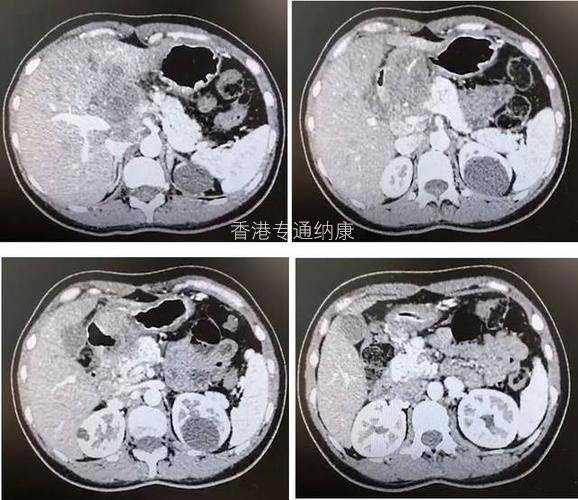

经研究显示,胃癌患者中约1/5呈HER2阳性。因此在DESTINY-Gastric01的II期临床试验中,评估了DS-8201在HER2阳性晚期胃或胃食管交界处(GEJ)腺癌患者中的有效性。

纳入188例接受过至少两次治疗的HER2阳性胃或胃食管交界处腺癌患者,研究结果显示:

客观缓解率(ORR):DS-8201组的为40.5%,而化疗方案组(伊立替康或紫杉醇组)仅为11.3%;

中位无进展生存期(PFS):分别是5.6个月和3.5个月;

中位缓解持续时间(DoR):分别为11.3个月和3.9个月;

中位总生存期(OS):分别为12.5个月和8.4个月。

在HER2、晚期胃或胃食管交界癌患者中,DS-8201的客观缓解率明显高于常规化疗,总生存期较常规化疗更长,与化疗方案相比其死亡风险降低41%(HR=0.59)。